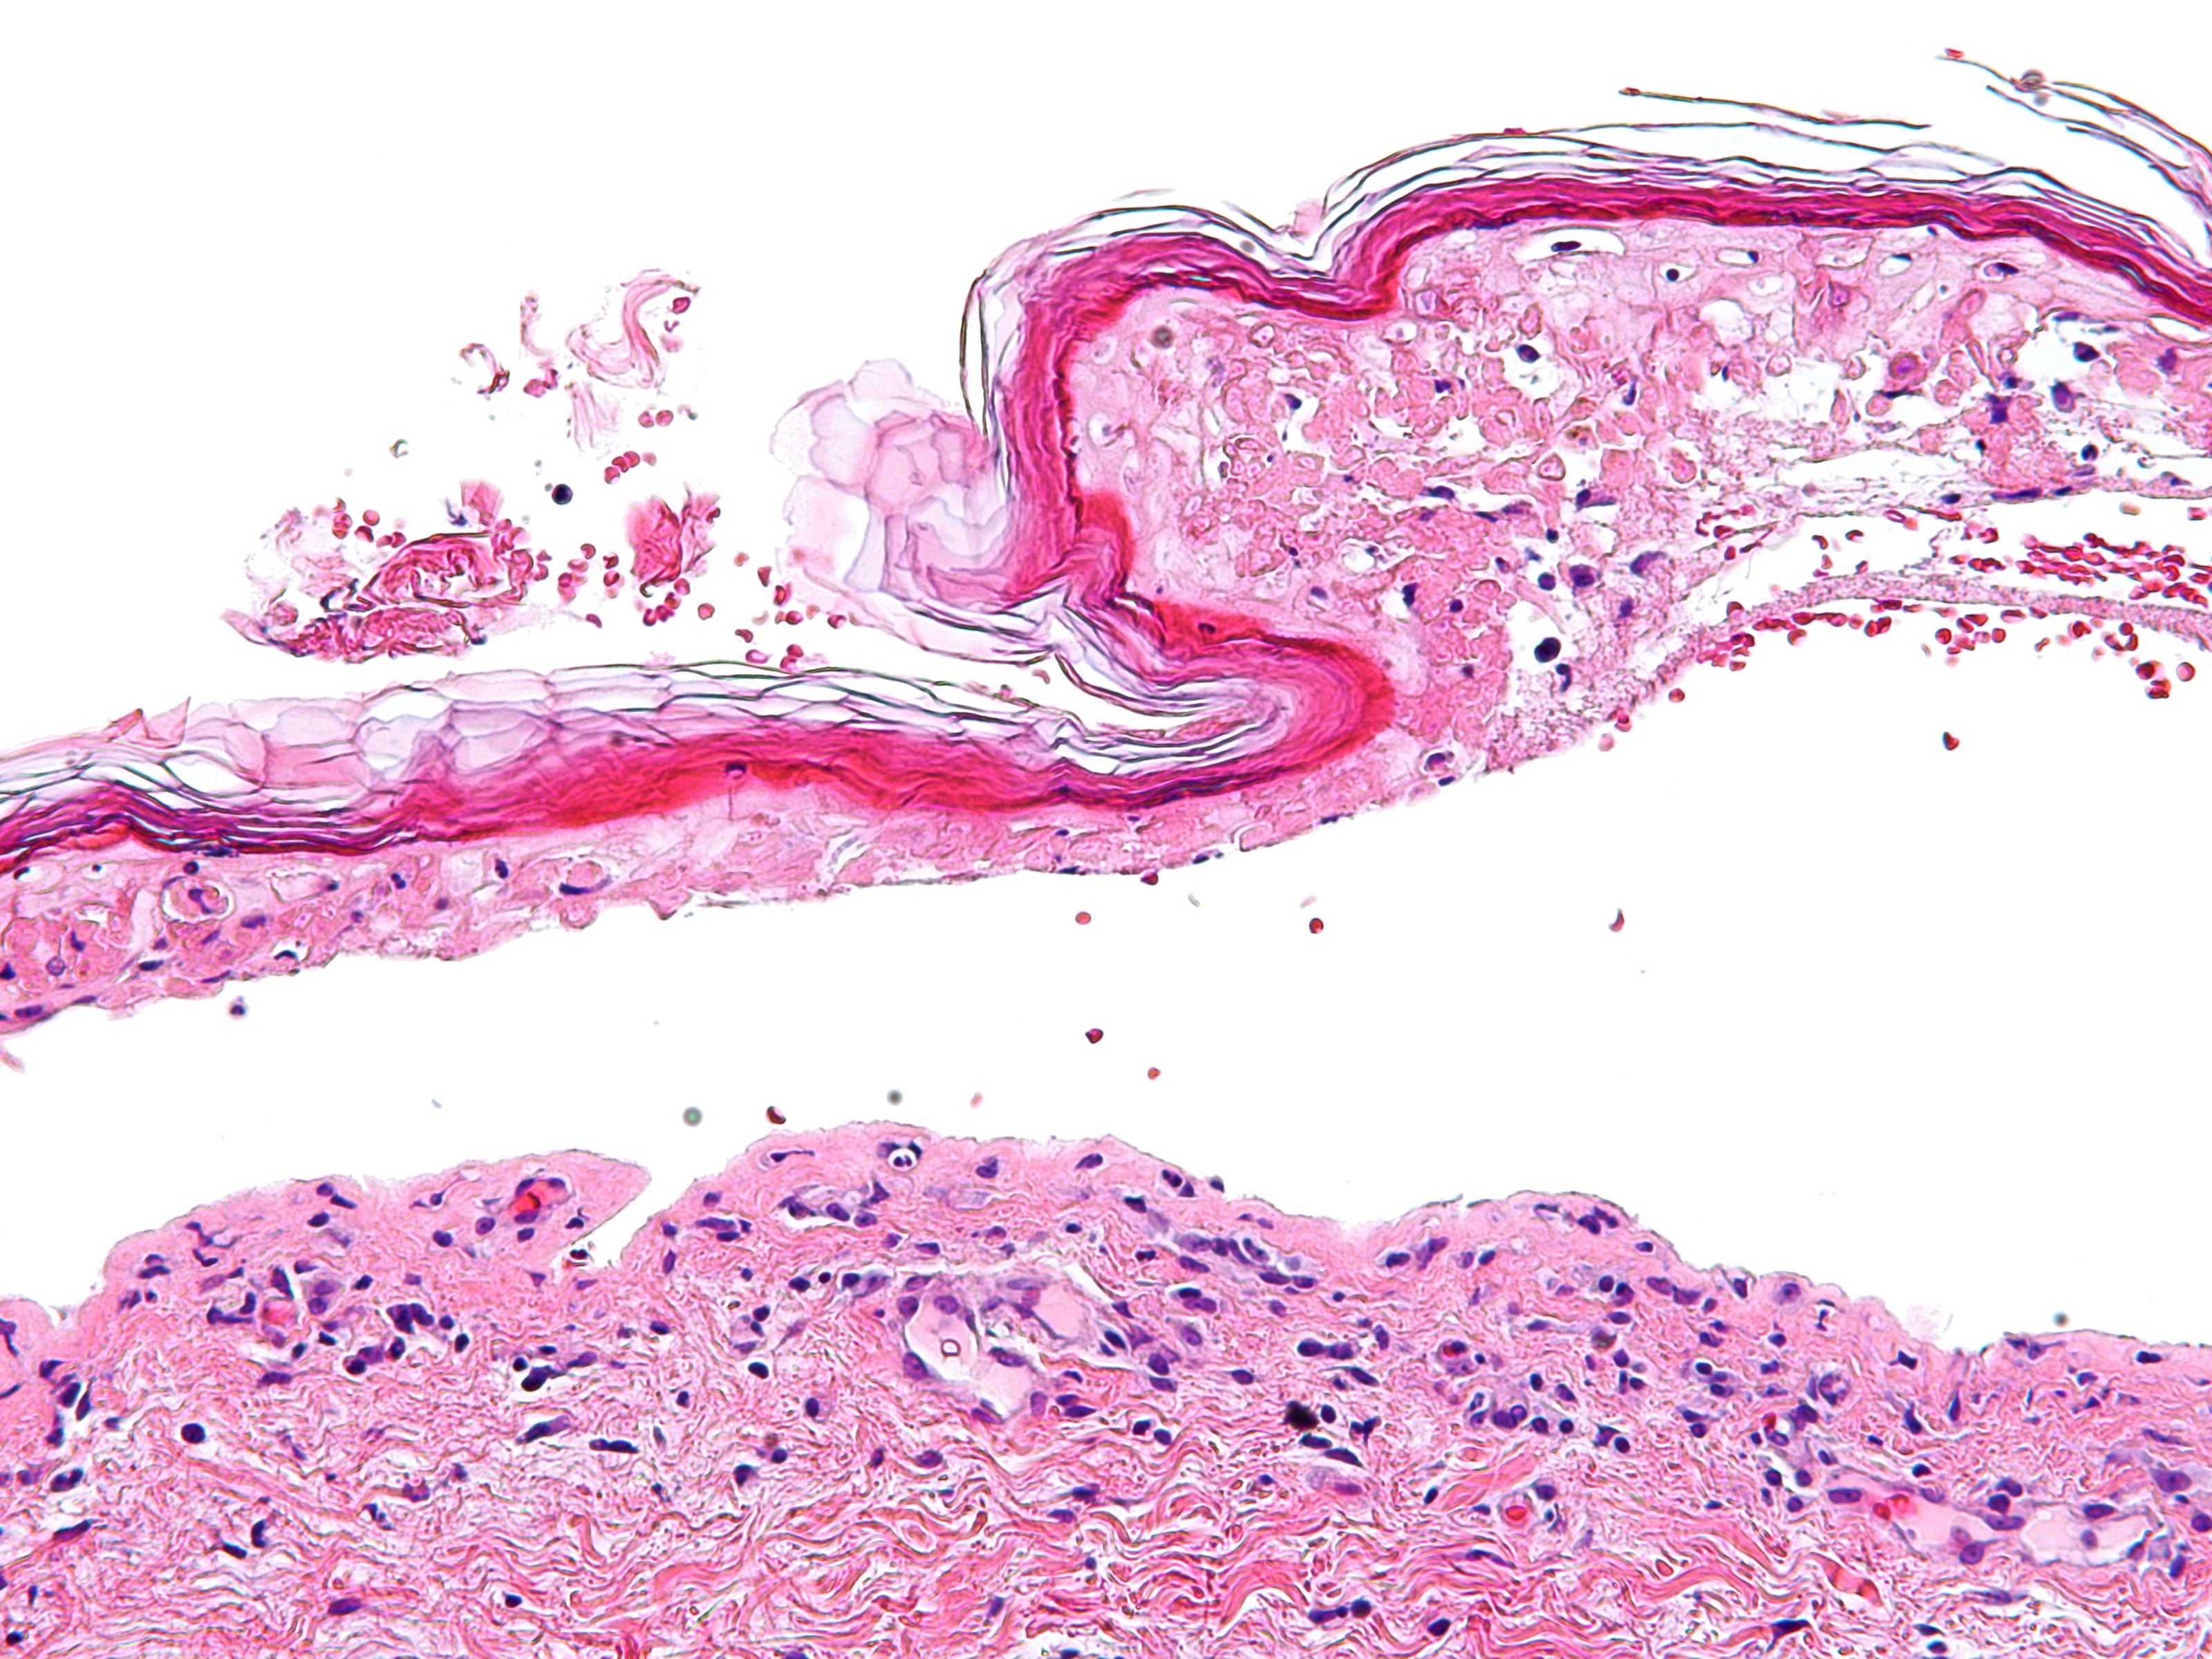

Histologisch

onderzoek: Vroege laesies van SJS en TEN: apoptotische keratinocyten

verspreid in de basale en direct suprabasale lagen van de epidermis. In latere

stadia: sub-epidermale splijting overdekt met confluerend necrose van de gehele

epidermis. Er is een spaarzaam / mild perivasculair ontstekingsinfiltraat, met

name bestaand uit lymfocyten. Immunopathologie: variabele aantallen lymfocyten

(CD 8+) en macrofagen epidermaal, lymfocyten (CD 4+) in de papillaire dermis.

![Toxische epidermale necrolyse (TEN) (click on photo to enlarge) [source: Michael Bonert (Nephron) - Wikimedia - Creative Commons License 3.0] Toxische epidermale necrolyse (TEN)](../../../images/SJS-PA-1z.jpg) |

| PA SJS

/ TEN |